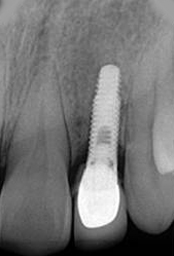

X-ray of Implant

Single Tooth Implant